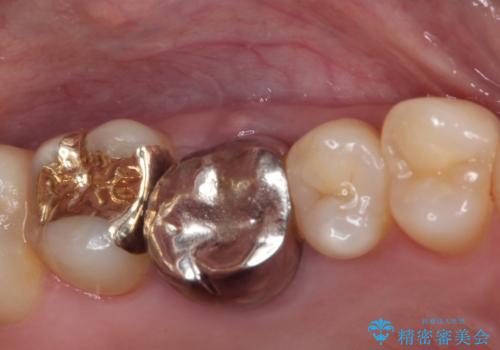

- 奥歯にものが挟まって痛みがあるとのことで来院された患者様です。

目視でも分かるくらいの欠損があり、歯の内部にむし歯が進行している状態でした。

上顎奥歯で目立たないことから、ゴールドインレー(PGAインレー)による修復治療をおこなうこととしました。